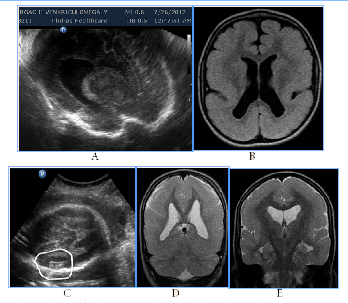

All cases with prosencephalic malformations had an adverse catamnesis connected with combined pathology. Two cases of alobar holoprosencephaly (HPE) and syndromic semilobar HPE were connected with perinatal losses. Syndromic lobar HPE with partial callosal agenesis and septo-optic dysplasia didn't have perinatal consequences, but the clinical outcome for the child was unfavorable as well (Figure1). HPE in 3rd trimester, 4 cases:

Figure 1 HPE in 3rd trimester, 4cases.

А) Alobar syndromic HPE with the residual mantle of the cortex at the base of the brain, severe progressive disgenetic hydrocephalus with macrocrania, intranatal death, clinical intranatal mismatch of head and pelvic size, fetus-damaging operation.

B) Isolated alobar HPE, cup-shaped type, the biggest part of the cortical mantleis attended, but it does not cover a single ​​anterior ventricular area, infant death.

C, D, E). Semilobar syndromic HPE with callosal agenesis. The ventricles are connecting through a narrow channel across the midline, thalamuses partially fused, IUGR, absent umbilical end-diastolic flow, antenatal death.

F). Fetal NSG and MRI of the newborn with syndromic lobar HPE, partial callosal agenesis, septo-optic dysplasia, US variant with merged, widely separated narrow acute-angled anterior horns of ventricular and dilated Verga’s cavity, long-term neurological disorders, severe visual impairment, epilepsy in the kid.